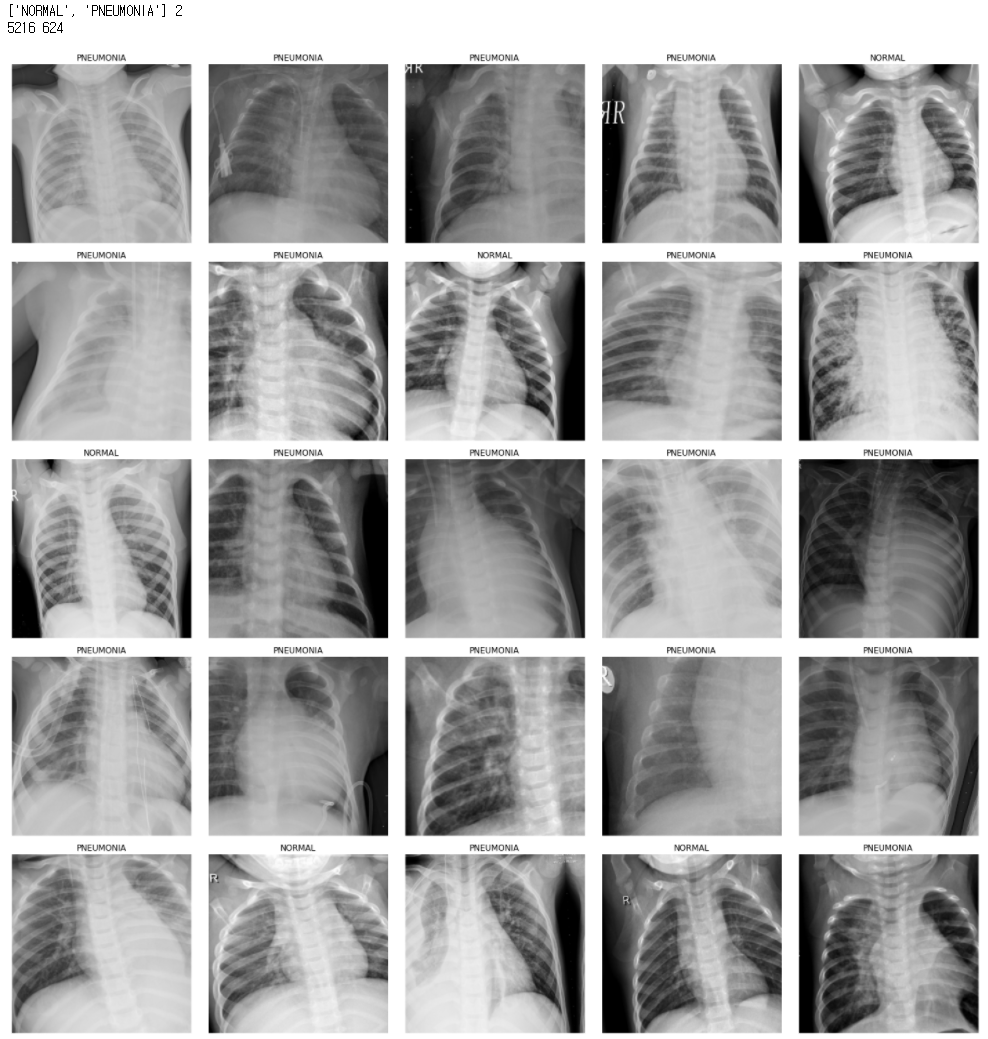

4. 데이터를 확인해보자.

# 위 get_transforms() 함수로 변형된 이후의 이미지를 출력

data.show_batch()

# 클래스 명칭과 클래스 개수를 출력

print(data.classes, data.c)

# train과 valid 데이터 개수 확인

print(len(data.train_ds), len(data.valid_ds))

클래스는 NORMAL, PNEUMONIA 두 개가 있고

학습 데이터는 5216개 평가 데이터는 624개가 있는 것을 확인할 수 있다.